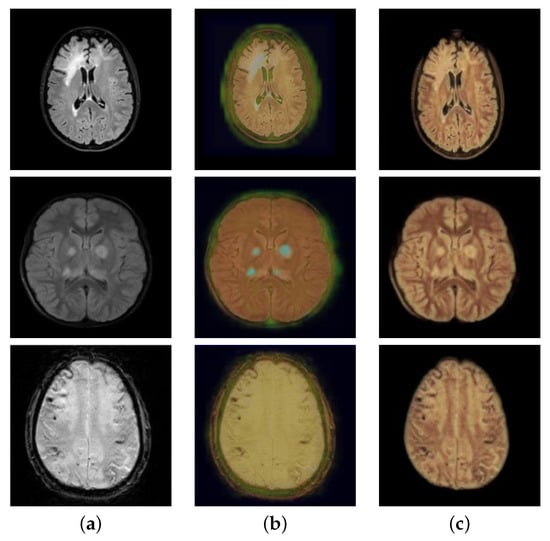

3.2. Comparisons with State-of-the-Art Networks

| Model | SSMI ↑ | PSNR ↑ | FID ↓ |

|---|---|---|---|

| colorCycleGAN | 0.69 | 19.86 | 163.65 |

| CycleGAN | 0.28 | 11.01 | 266.58 |

| Zhang’s | 0.89 | 32.45 | 104.72 |

| ChromaGAN | 0.89 | 27.48 | 125.65 |

| Ours | 0.90 | 33.22 | 84.81 |